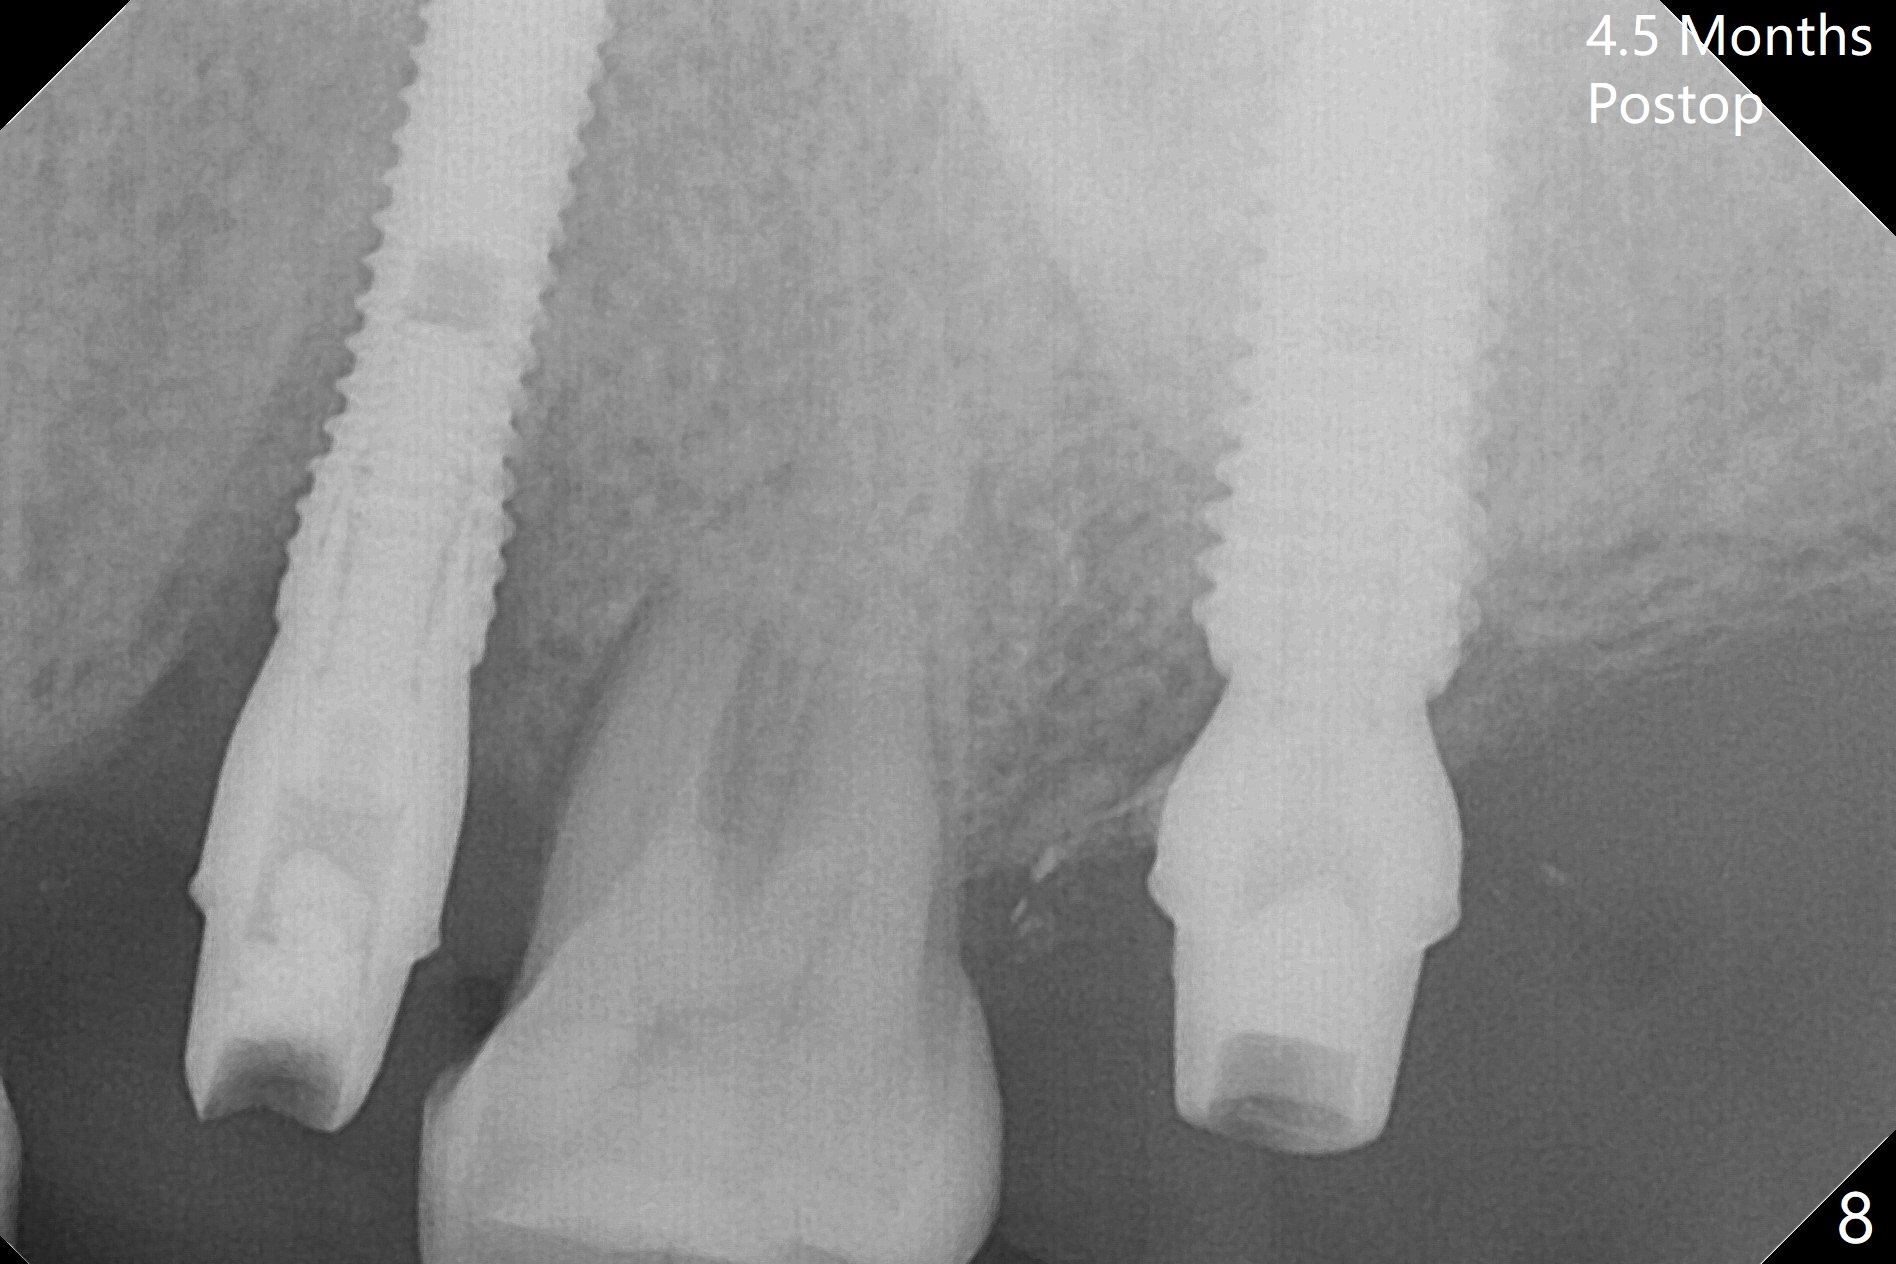

A 1.2 mm initial drill is used to start osteotomy at the site of #15 (Fig.1). After moving the osteotomy distally (with Lindamann bur), the osteotomy is enlarged by DIO Bone Expanders until 2.4/3.7 mm for 18 mm (gingival level) (Fig.2). Following the expander 3.0/4.4 mm, a 5x13 mm UF implant is placed supracrestal (Fig.3,4). After deepening the osteotomy with 3.8 mm drill for 3 mm, the implant is placed deeper by ~ 2 mm (Fig.5 arrow). Since the tooth #18 is supraerupted, a healing abutment (5.5x12(3) mm) is placed (Fig.6: H); the gingiva adapts to the abutment well. Suture is not necessary. The bone remains stable 2 and 4.5 months postop (Fig.7,8). Impression is taken. A crown is delivered nearly 6 months postop (08/07/2017). While there is minimal bone loss at #13 and 15 three years and 4 months post cementation, the tooth #14 and 18 are mobile (Fig.13,14, #13).